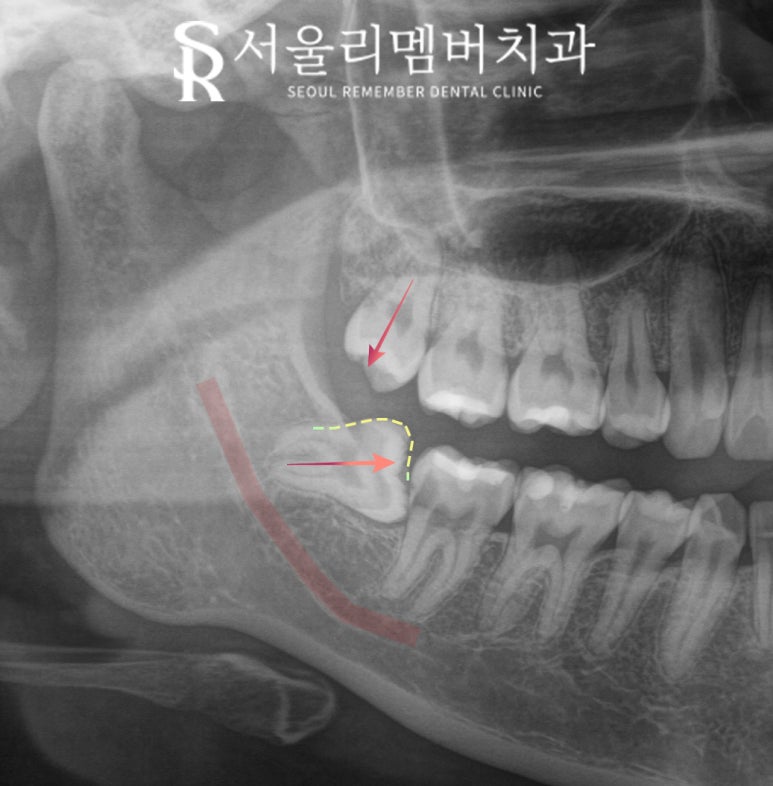

오늘 서울대입구역 치과 에서

보여드리는 케이스는

오른쪽 위아래 사랑니가 모두 존재하는데

하악 제3대구치는 앞으로 기울어져

저작기능을 수행할 수 없으며

되려 그 틈으로 음식물이 끼게 만들고 있습니다.

사랑니 발치의 경우,

파노라마 엑스레이를 찍어봐야

말씀드릴 수 있습니다.

만약 하치조 신경관과 겹쳐있거나

거리가 너무 가까이 있다면 어려울 수 있고

이 케이스는

하치조 신경과의 거리도 넉넉하고

상악의 경우 수직으로 잘 자라있어

둘 다 당일에 바로 뽑아드렸으며

출혈도 크지 않아

suture 즉, 꿰매지 않고

바로 마무리할 수 있었네요.